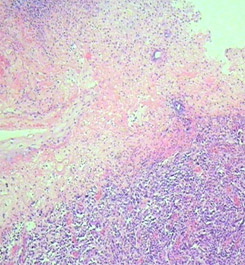

Гистологическое исследование меланомы предусматривает определение параметров, влияющих на клиническое течение («biologic behaviour») меланомы и прогноз заболевания: форма роста, гистологический вариант, наличие/отсутствие пигмента, толщина опухоли по Бреслоу (A.Breslow, 1970), уровень инвазии по Кларку (W.Clark, 1967), а также таких характеристик как наличие изъязвления, митотический индекс, сосудистая (ангиолимфатическая) инвазия, выраженность лимфоидной инфильтрации, проявления спонтанной регрессии, наличие сателлитов*), транзитных**) (и других) метастазов. При гистологическом исследовании также оценивается наличие/отсутствие элементов опухоли по краю удаленного фрагмента кожи.

Наиболее важными факторами прогноза являются толщина опухоли по Бреслоу и изъязвление; для опухолей толщиной менее 1,0 мм учитываются уровень инвазии по Кларку и митотический индекс (рис. 1).

Толщина опухоли по Бреслоу измеряется в миллиметрах с помощью оптического микрометра. При этом учитывается уровень инвазии по Кларку и максимальная толщина опухолевого узла. Изъязвлением считается отсутствие эпидермиса над опухолью. При этом определяются поверхностные грануляции, зоны некроза, фиброзно-лейкоцитарные наложения (эрозирование поверхности с сохранением части слоев эпидермиса не является изъязвлением). Митотический индекс оценивается по максимальному количеству митозов в 1 мм2.

Рис. 1. Наиболее важные морфологические факторы прогноза.

А) Схема определения уровня инвазии по Кларку (W.Clark, 1967);

Б) Схема определения толщины опухоли по Бреслоу (A.Breslow, 1970);

В) Гистологическая картина изъязвления;

Г) Оценка митотического индекса.